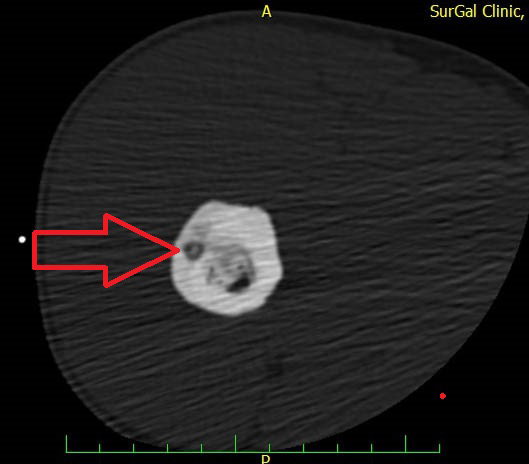

Obr. 5. Nidus osteoidního osteomu v krčku levé kyčle na RTG snímku

Obr. 6. RFA osteoidního osteomu levé kyčle a CT kontrola po roce